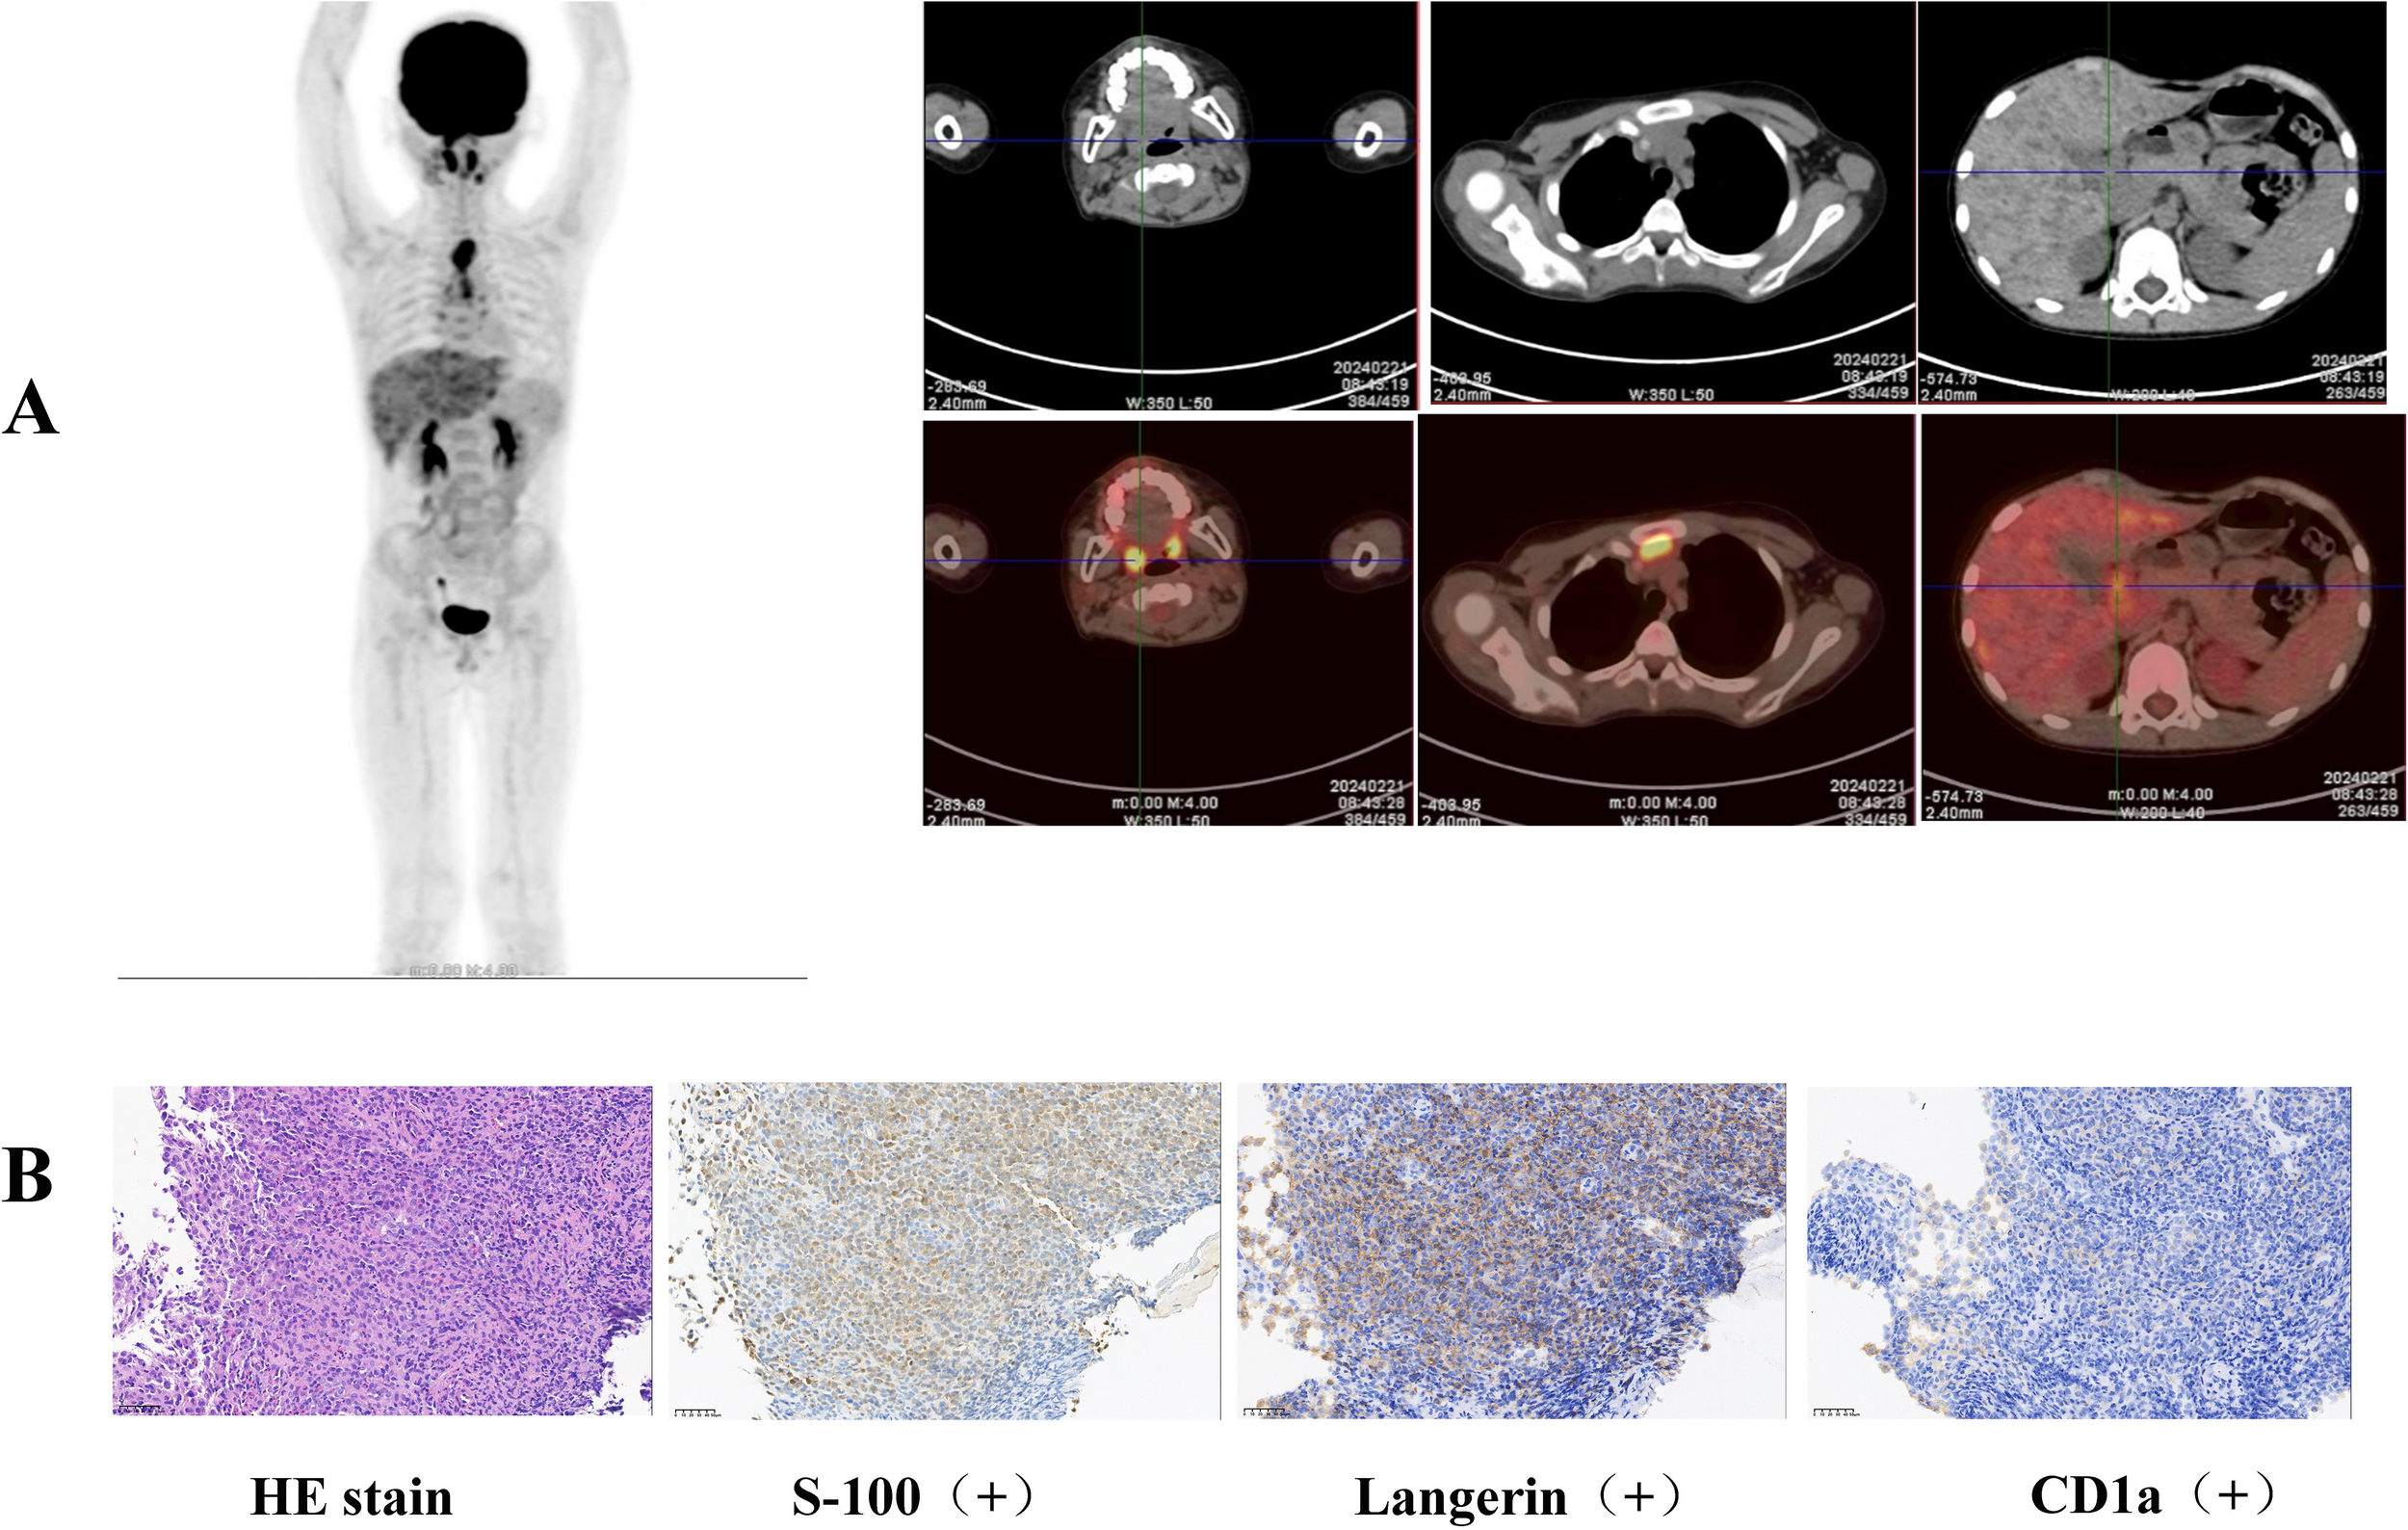

Figure 2. (A) Elevated FDG metabolism was detected in the gastric body, gastric antrum, nasopharynx, left submandibular gland, lymph nodes, thymus, and liver by whole-body FDG PET/CT examination. (B) Pathological biopsies revealed atypical cells in the gastric antrum expressing CD 1a, S-100, and Langerin.

LCH was diagnosed based on the clinical manifestations, pathological biopsy, and genetic examination. Whole-body FDG PET/CT revealed elevated FDG metabolism in the gastric body, gastric antrum, nasopharynx, left submandibular gland, lymph nodes, thymus, and liver (Figure 2A). Therefore, the patient was diagnosed with high risk organ involvement (RO+) multisystem LCH. LCH III-directed induction chemotherapy (prednisone, 40mg/m2/d orally, day1-28, afterwards weekly reduction; vincristine, 2mg/m2/d, iv, bolus, day1, 8, 15, 22, 29, 36) was administered. Due to the unavailability of vinblastine in China, vincristine was utilized as a substitute. After 1 week of chemotherapy, the patient’s abdominal pain disappeared. After 6 weeks of induction chemotherapy, gastroscopy revealed that the number of lesions in the stomach and esophagus had significantly reduced (Figure 1B).

The patient was referred to our hospital for further treatment. This was due to the rarity of gastric lymphoma during childhood. Due to the patient’s inability to acquire pathological biopsy tissue from the initial hospital in a timely manner, we opted to perform a repeat gastroscopy to obtain tissue for biopsy. We could still clearly observe gastric nodules and ulcers (Figure 1A). Pathological biopsies of the esophagus, descending duodenum, gastric antrum, gastric angle, and descending duodenum were performed. The results revealed atypical cells in the gastric antrum expressing CD 1a, S-100, and Langerin (Figure 2B). Furthermore, we detected 38 LCH-related genes, including KRAS, ARAF, ERBB2, MAP2K1, ERBB3, MAP2K2, and BRAF. Moreover, the patient harbored a deletion mutation in exon 12 of BRAF(c.1457_1471del), which led to an amino acid deficiency at positions 486 to 490.